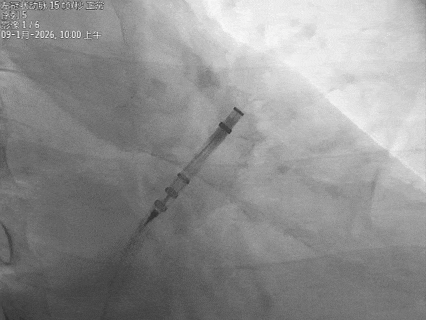

保持输送系统张力,退鞘使封堵器展开,封堵器锚定位置良好

封堵器骨架和鞘管、心耳长轴的同轴性良好,持续退鞘,封堵器充分展开

封堵器展开后造影

封堵器展开后肝位造影,封堵器完全封堵,无残余分流